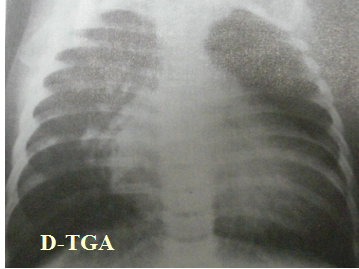

正常心脏胸部正位片示意图(A-P) 正常心脏胸部侧位片示意图(Lateral)

X-Ray --心脏形状